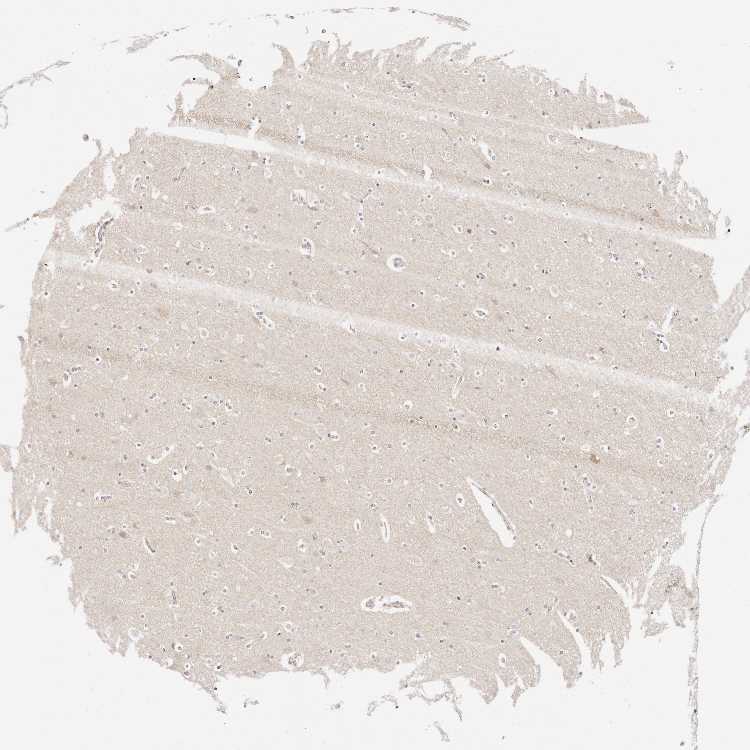

AFDN